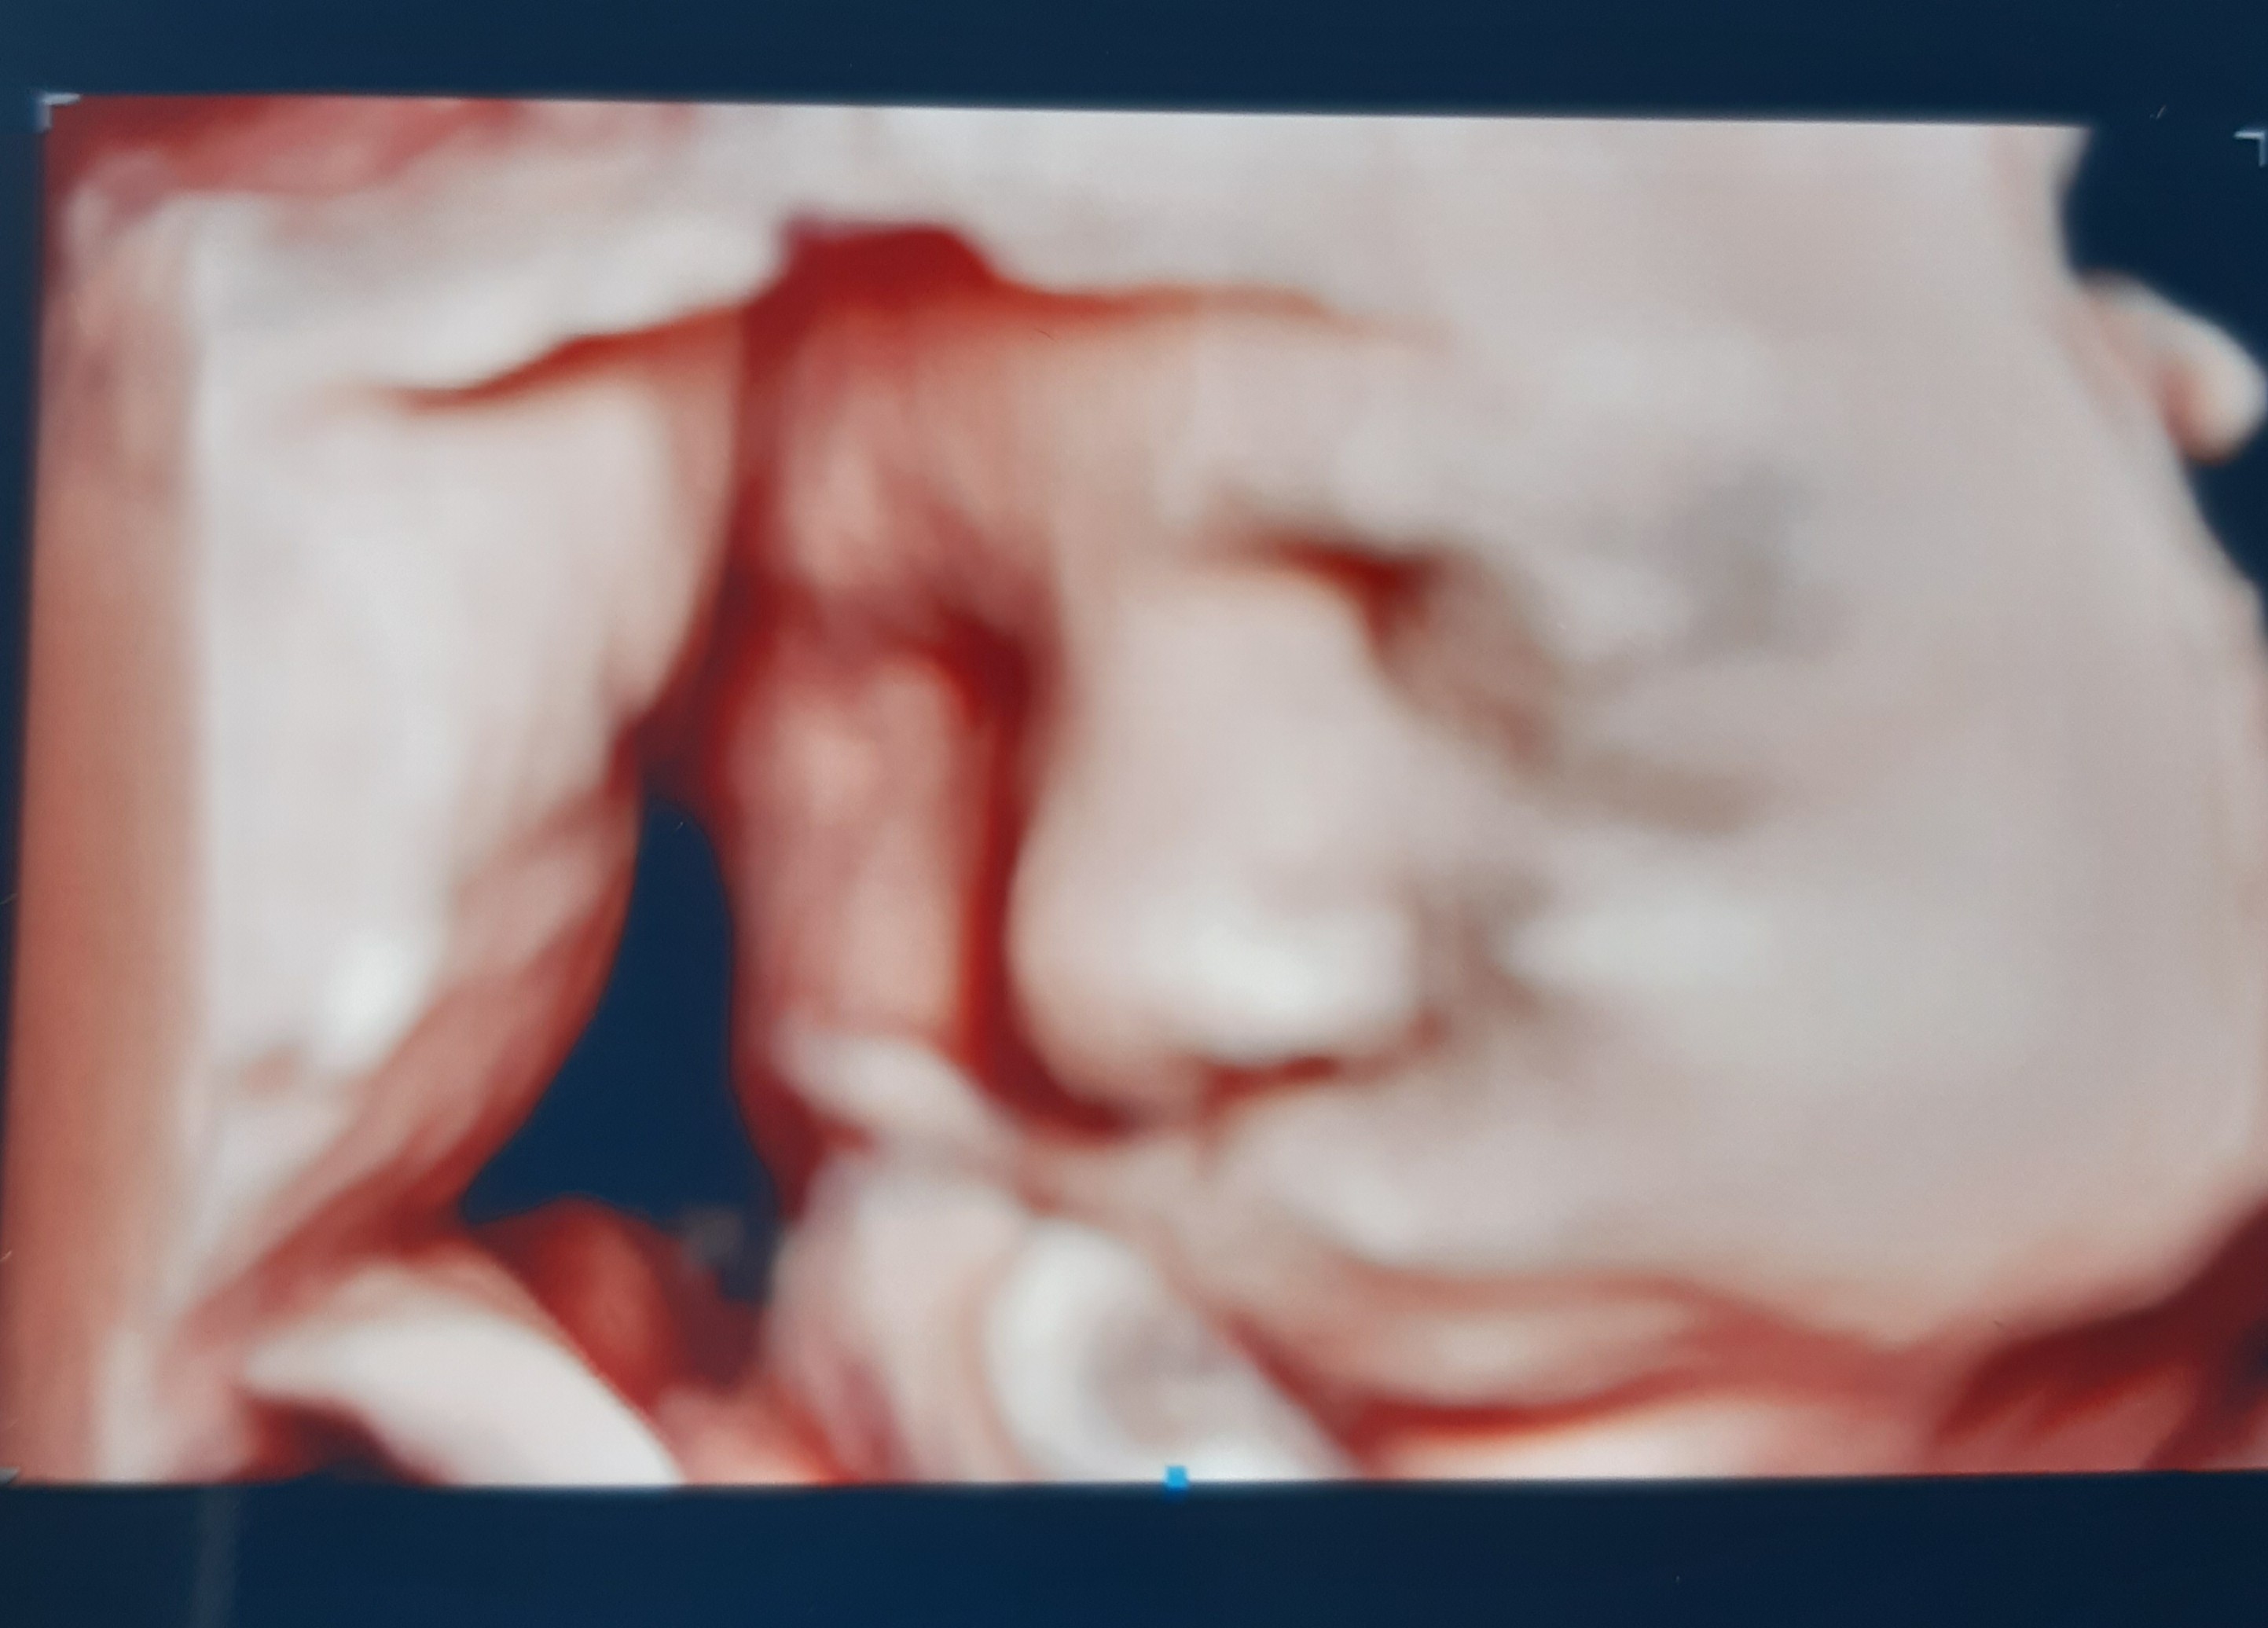

Byłam dzisiaj prywatnie na USG 3 trymestru. I tutaj pomiar wskazuje na ok.1,5kg kobitki😊 także ten z wtorku troszkę zawyżony, ale wiadomo zależy od sprzętu. Sam lekarz mówił, że właśnie w dobre usg mają najlepszy sprzęt w Krk. Nie byko latwo, bo mala sie zakrywała, ale w końcu się pokazała😊